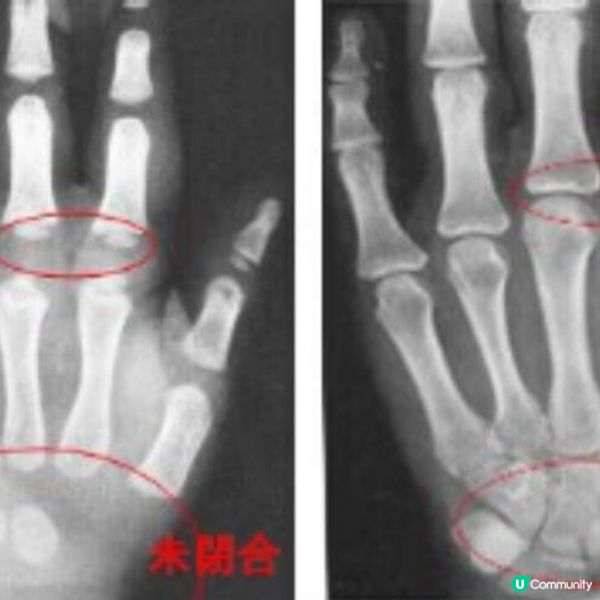

生長板的迷思!成年後仍可長高嗎?